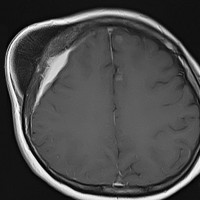

上矢状洞髄膜腫 superior sagittal sinus meningioma

また別な例です。1986年13歳の時に2度の開頭手術を受けましたが,全摘出できずにそのまま経過観察されました。

左の画像は1997年の術前のものです。これを2回に分けて全摘出しました。上矢状洞はやはり冠状縫合のあたりから静脈洞交会まで摘出しました。その下の大脳鎌も全て摘出したので,直静脈洞の上壁を開けることになり,直静脈洞からの激しい出血があり縫合して直静脈洞形成をするのが大変でした。手術後16年が経過しますが再発していませんし,社会人として普通に暮らせています。

この例が教えてくれることは,上矢状静脈洞は全長にわたり切除してしまっても,神経脱落症状を出さないで普通に生きて行かれるということです。